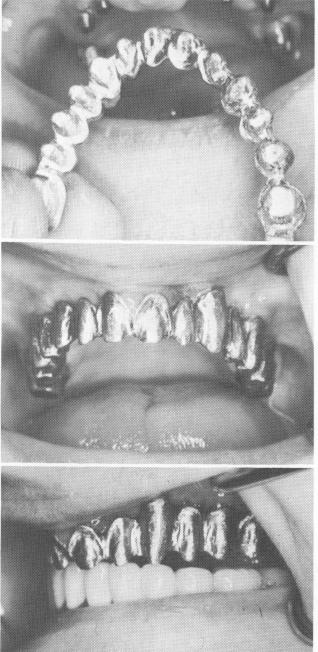

Fig. 11-127. A cold cure acrylic splint made from the patient's old denture was used for temporary stability.

Fig. 11-128. Six days later the tissues had healed sufficiently around the implants to allow removal of the sutures. The inflammation of the anterior soft tissues was caused by the impingement from the ill-fitting temporary splint.